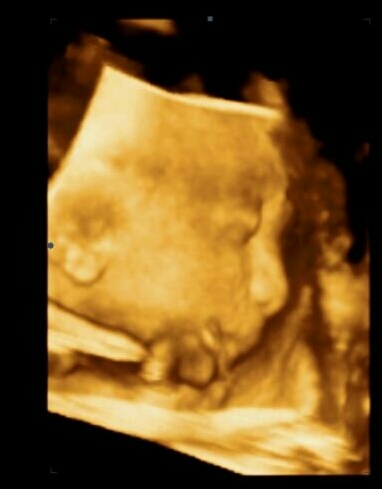

Ahoj holky, včerejší kontrola za mnou, cukrovka dopadla dobře. Chtěla jsem 3D fotku a holčička ukazovala jen zádíčka, pak jsem jukla tak jedna fotka z profilu. Jinak mi trápí močák. Taky kýcham a vždy se pripočurnu. Tě to nepříjemné. Taky tlak na spodek hrozný.